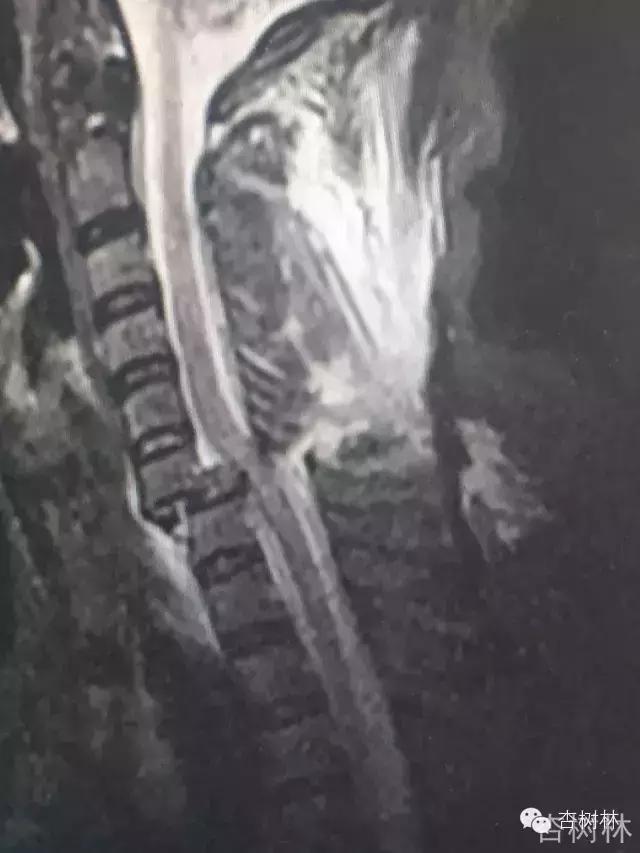

影像:急诊CT及MRI检查提示如下。

专家点评概述: 颈椎脱位 (C6-7 )伴不全瘫 ; 颈脊髓损伤 AISA B 级 ; C6-7 关节突关节绞锁(双侧)的关键点